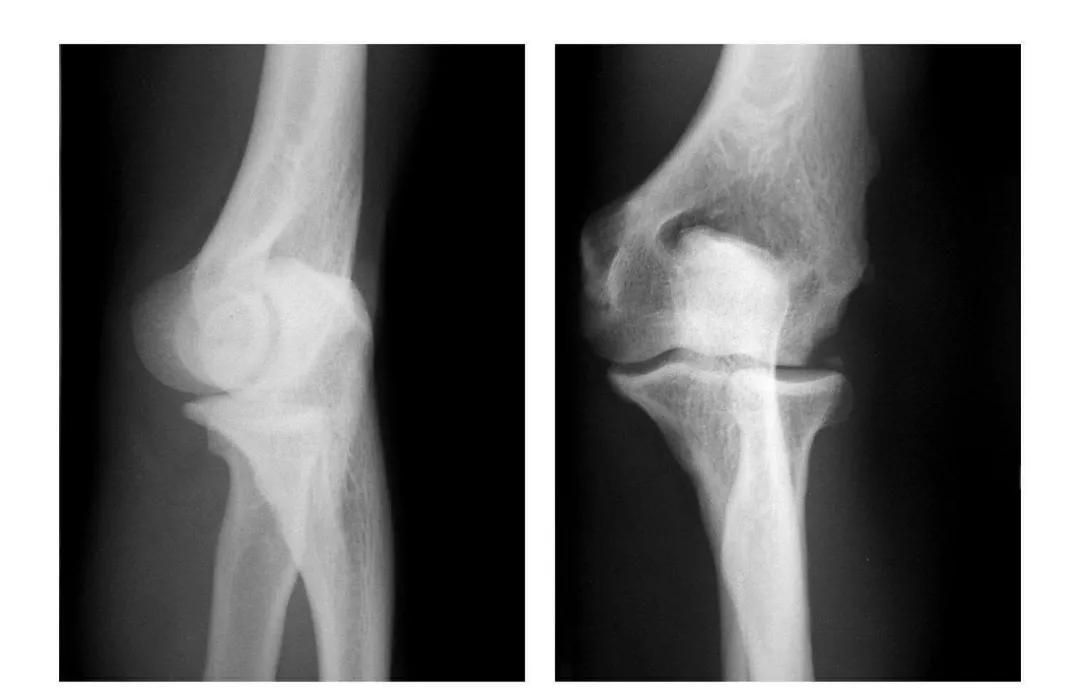

肱骨小头冠状面骨折

(一)完全骨折

本病亦称哈-斯(Hahn-Steinthal)型骨折

例1:肱骨小头基底部呈冠状面骨折,骨折块呈半球状向肘前上方移位。

例2:肱骨小头基底部冠状面骨折,骨折块呈半球状向肘前移位并肱骨内上髁无移位骨折。